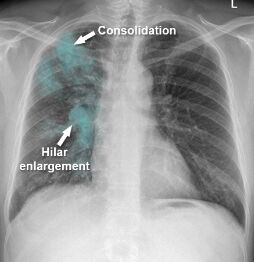

46.吳先生45歲,不抽菸,因咳嗽2個月至門診就醫,胸部X光檢查結果如圖所示,最可能的診斷為何?

(A)細菌性肺炎

(B)間質性肺炎

(C)肺結核

(D)肺癌

胸部x光可見雙側上肺野和近肺門處有間質性...